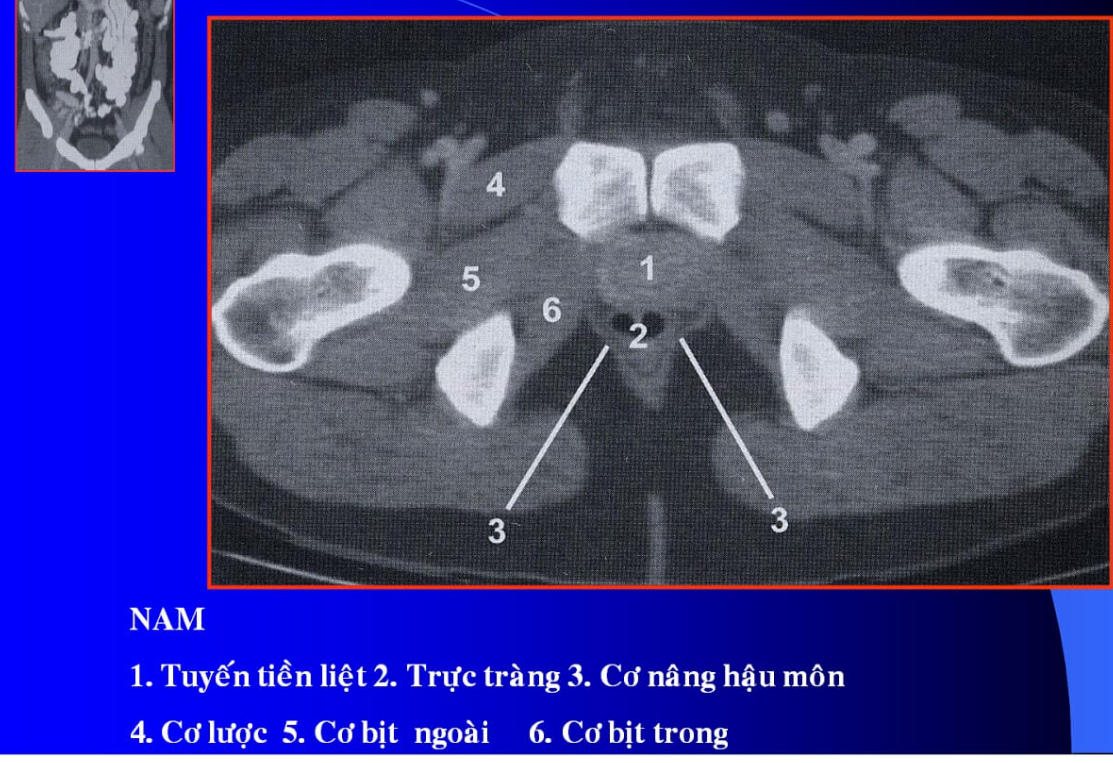

cq trong hình ?